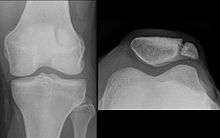

![]() Right knee | |